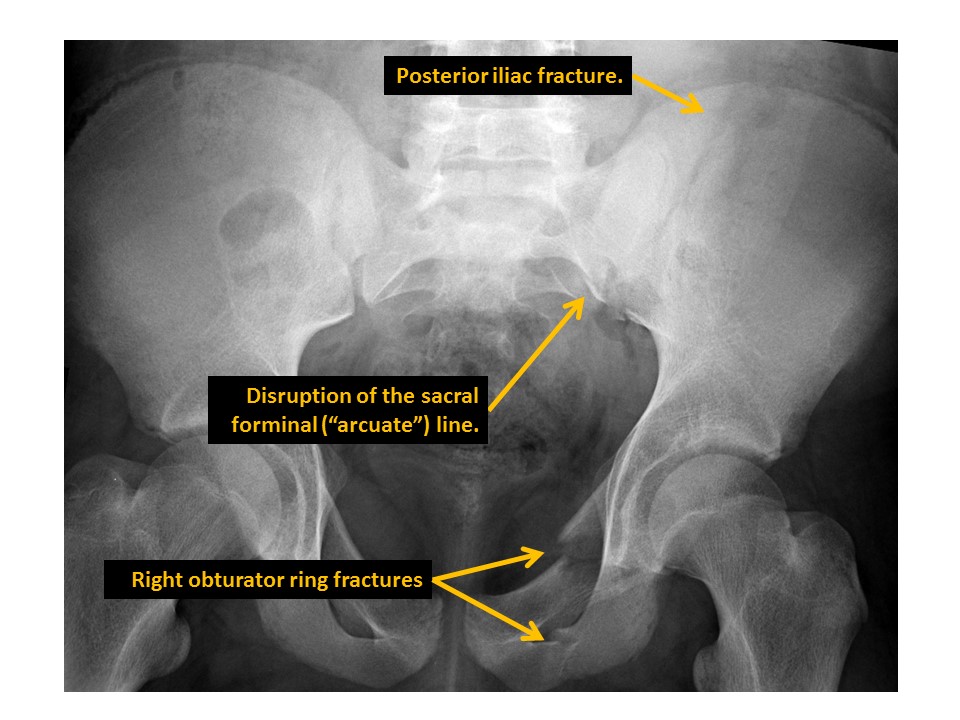

There are displaced fractures or disrupted/asymmetric foraminal arcs. [Yes/No]

There is a pubic ramus fracture. [Yes/No]

Posterior iliac bone fractures are present. [Yes/No]